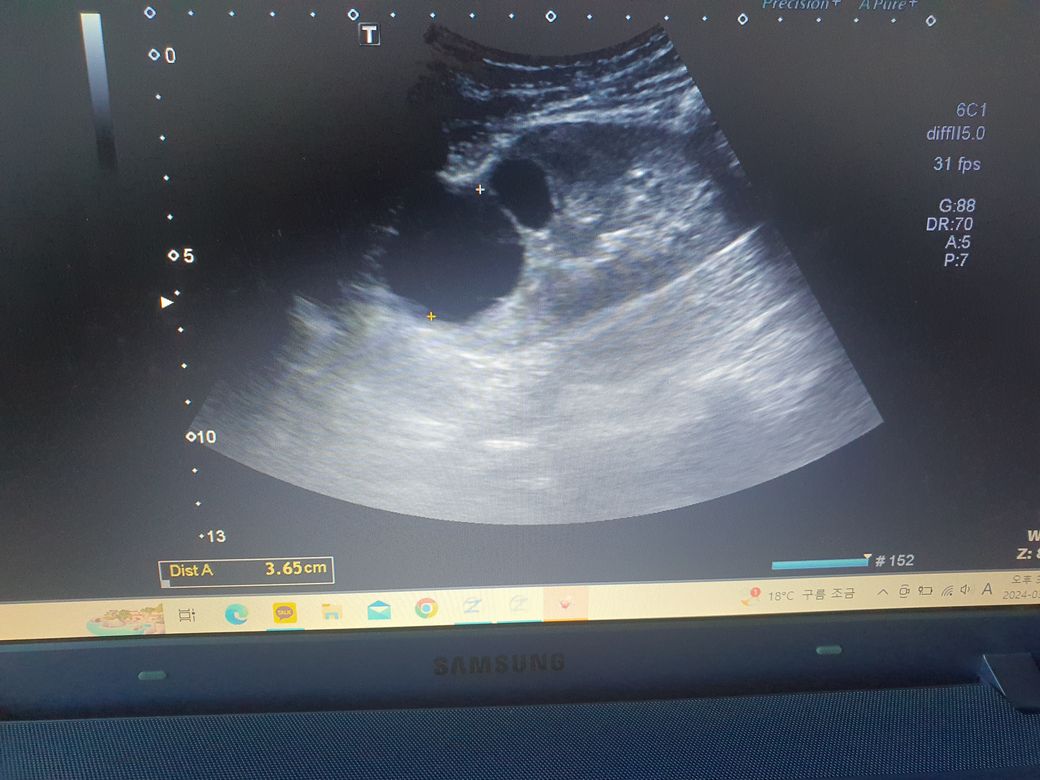

낭종 크기 3.6cm

• 2번 째 사진